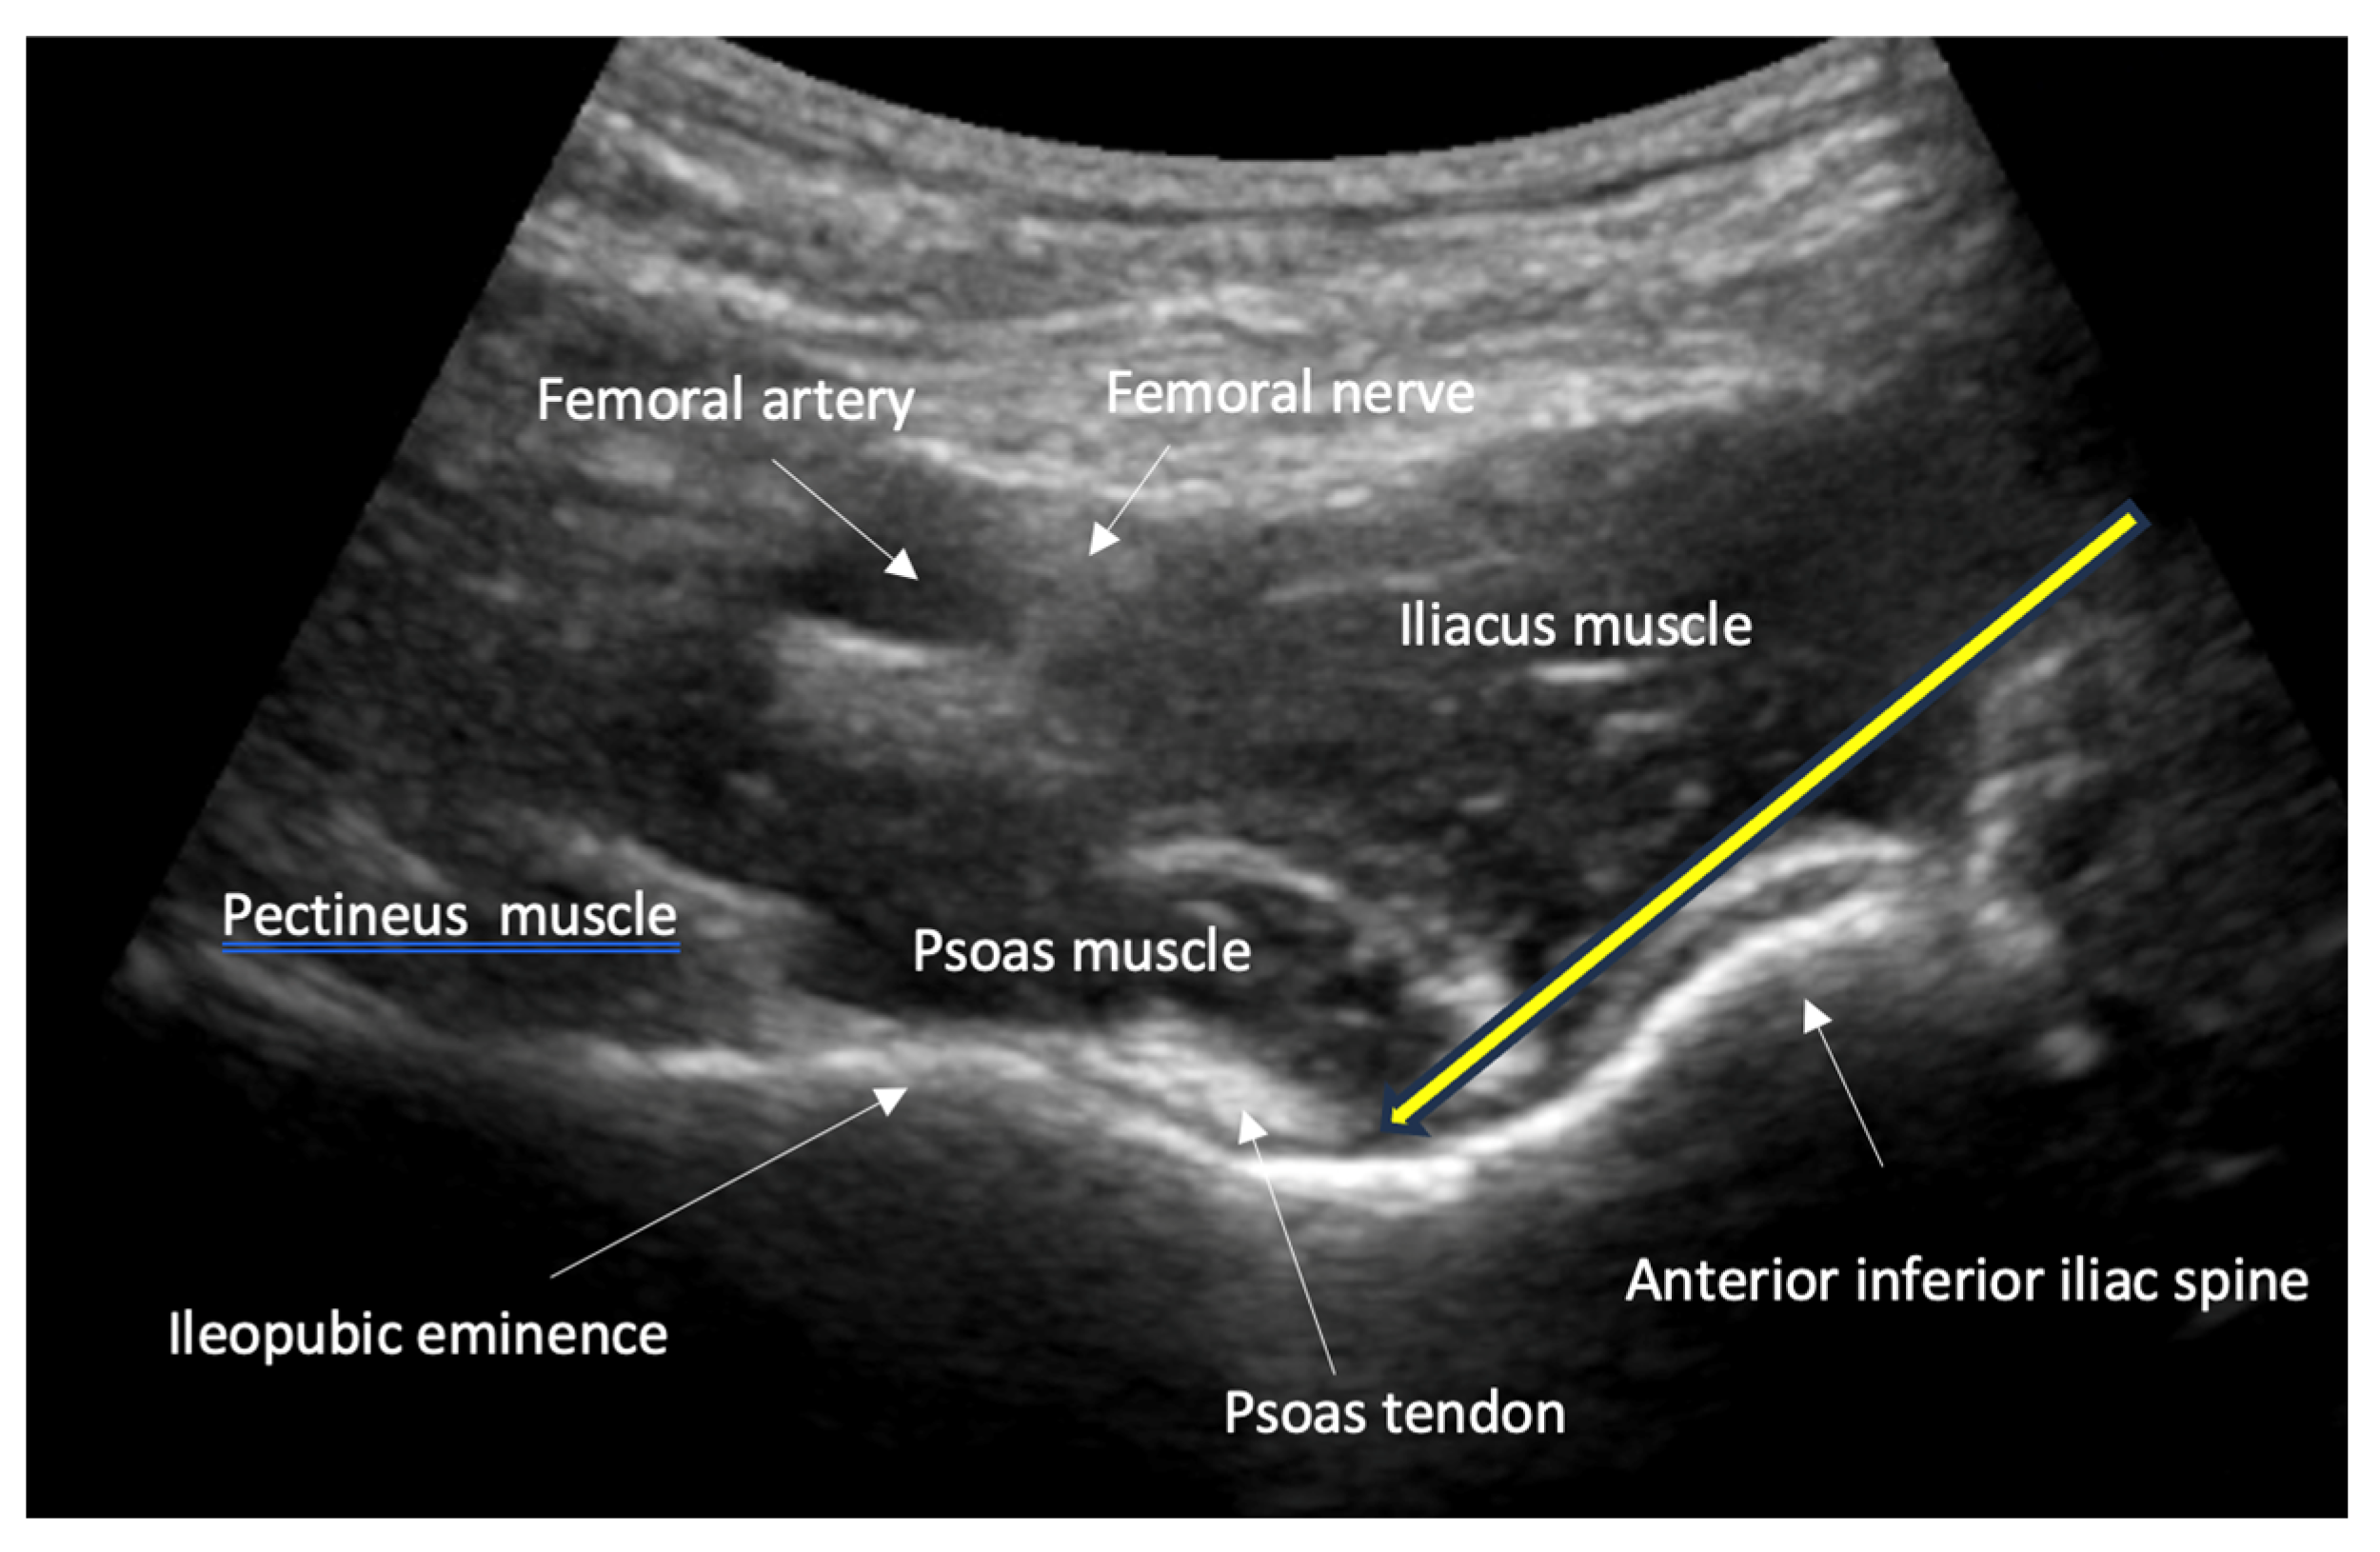

- Guidance of nerve blocks for pain management and regional anesthesia: ultrasound guidance improves the precision of nerve blocks, which are essential for pain control and safe repositioning of fractures.

- Nerve, fascia and fascial plane blocks

- Recommendation 8: Simple fascia and fascial blocks are highly suited for analgesia in patients with rib and femoral neck fractures. Local anesthesia using nerve blocks and fracture hematoma blocks should be preferred over analog sedation for fracture reduction whenever possible, as they are less risky.

- For simple fascia and fascial blocks, such as rib and femoral neck fractures. Local anesthesia using nerve blocks is preferred to analog sedation for fracture reduction.